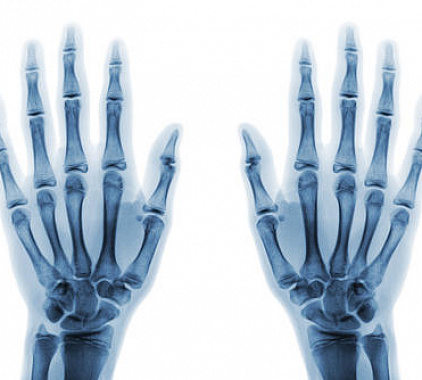

По итогу анализа полученных сведений доктор формирует подробный протокол. В нем врач указывает состояние костных тканей, суставов, суставных щелей, близко находящихся тканей. Доктор подробно описывает любые обнаруженные патологические изменения, отражает их главные особенности: стадия, характер поражения, вид, локализация, размеры и др. В конце рентгенолог пишет свое заключение.

Любая полученная информация в дальнейшем должна быть проанализирована лечащим врачом. Путем сопоставления готовых значений с анамнестическими данными, жалобами человека, доктор выставляет окончательный диагноз. На его основании специалист определяет вид лечения (хирургическое, консервативное), дает свои рекомендации, освещает вероятный прогноз.